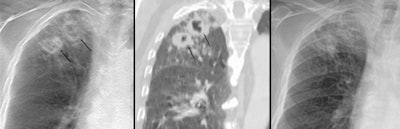

![]() |

| Two thick-walled cavities from an 80-year-old man with active pulmonary TB were seen in digital tomo image (left). They were confirmed on CT (center) but escaped detection in the radiograph (right). Images provided by Dr. M.J. Chung. |

For the presence of cavities, for example, tomosynthesis had a per-lesion sensitivity of 85%, characterizing 85 of the 100 cavities observed with CT. In comparison, general radiography identified 28 cavities, for a per-lesion sensitivity of 28%. Both modalities were responsible for three false-positive lesions in two patients.